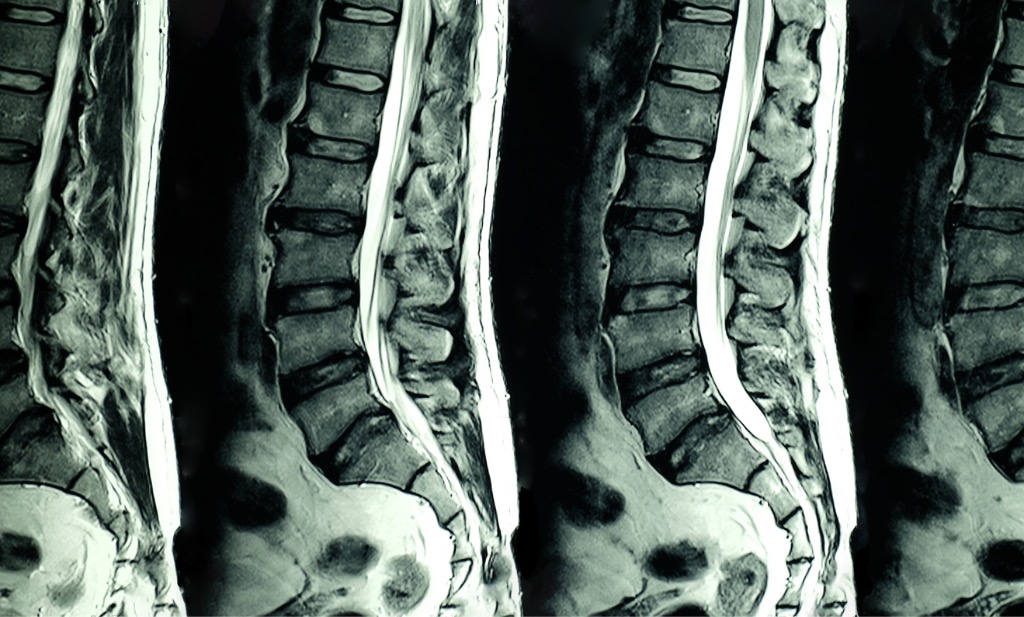

MRI scan of lumbar spines

Degenerative lumbar spine conditions, particularly at L4-5 and L5-S1, commonly refer pain to the hip. Iliotibial band syndrome and sacroiliac joint dysfunction may also cause referred hip pain. In your first visit, we will evaluate your symptoms, perform a physical exam, and may use imaging such as X-rays or diagnostic musculoskeletal ultrasound to reach an accurate diagnosis.